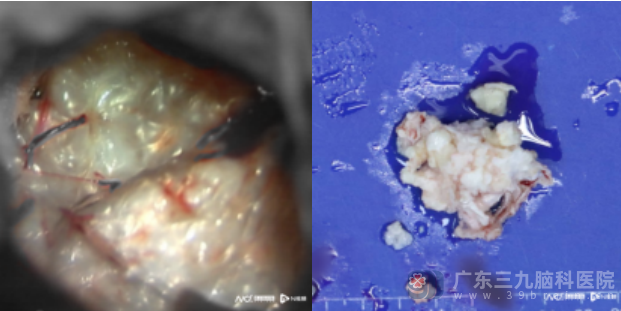

征得患者及家属同意后,12月6日,该院神经外二科团队为患者行神经内镜、显微镜双镜联合下枕大池-四脑室-双侧侧孔区占位病变切除术。“显微镜下,能看到肿瘤如同白色珍珠般。”参与手术的神经外二科张旭标副主任医师说道。术后病理诊断为胆脂瘤,证实了术前诊断。

镜下及切除的肿瘤。